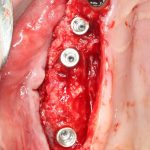

Я же в своей практике для создания доступа использую ультразвук, а именно — электрический пьезохирургический аппарат VarioSurg (NSK). Он позволяет делать очень красивый и практичный доступ любой формы:

Однако, почему я выбрал именно этот способ? Плюсы:

- это более безопасно, нежели использование бормашины.

- можно сделать доступ любой формы.

- после создания доступа получается костный фрагмент, который мы можем использовать по-разному (для закрытия перфорации, костной пластики,

- можно создавать большие доступы и закрывать их получившимся костный фрагментом, легко обходить септы, шипы и перегородки дна верхнечелюстной полости

- сам процесс создания доступа получается более контролируемым.